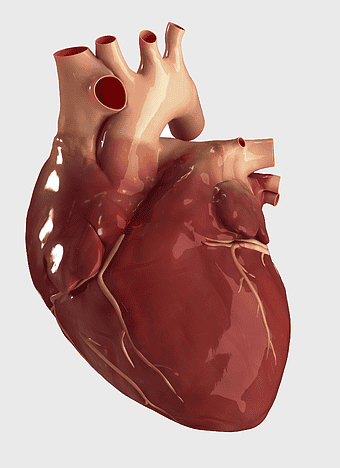

red heart anatomy, human heart drawing, cartoon heart illustration, love and biology, cardiovascular system diagram, medical art depiction, organ structure visualization -

human heart anatomy, cardiac muscle illustration, circulatory system model, heart health visual, cardiovascular organ diagram, medical heart image, visceral structure depiction -